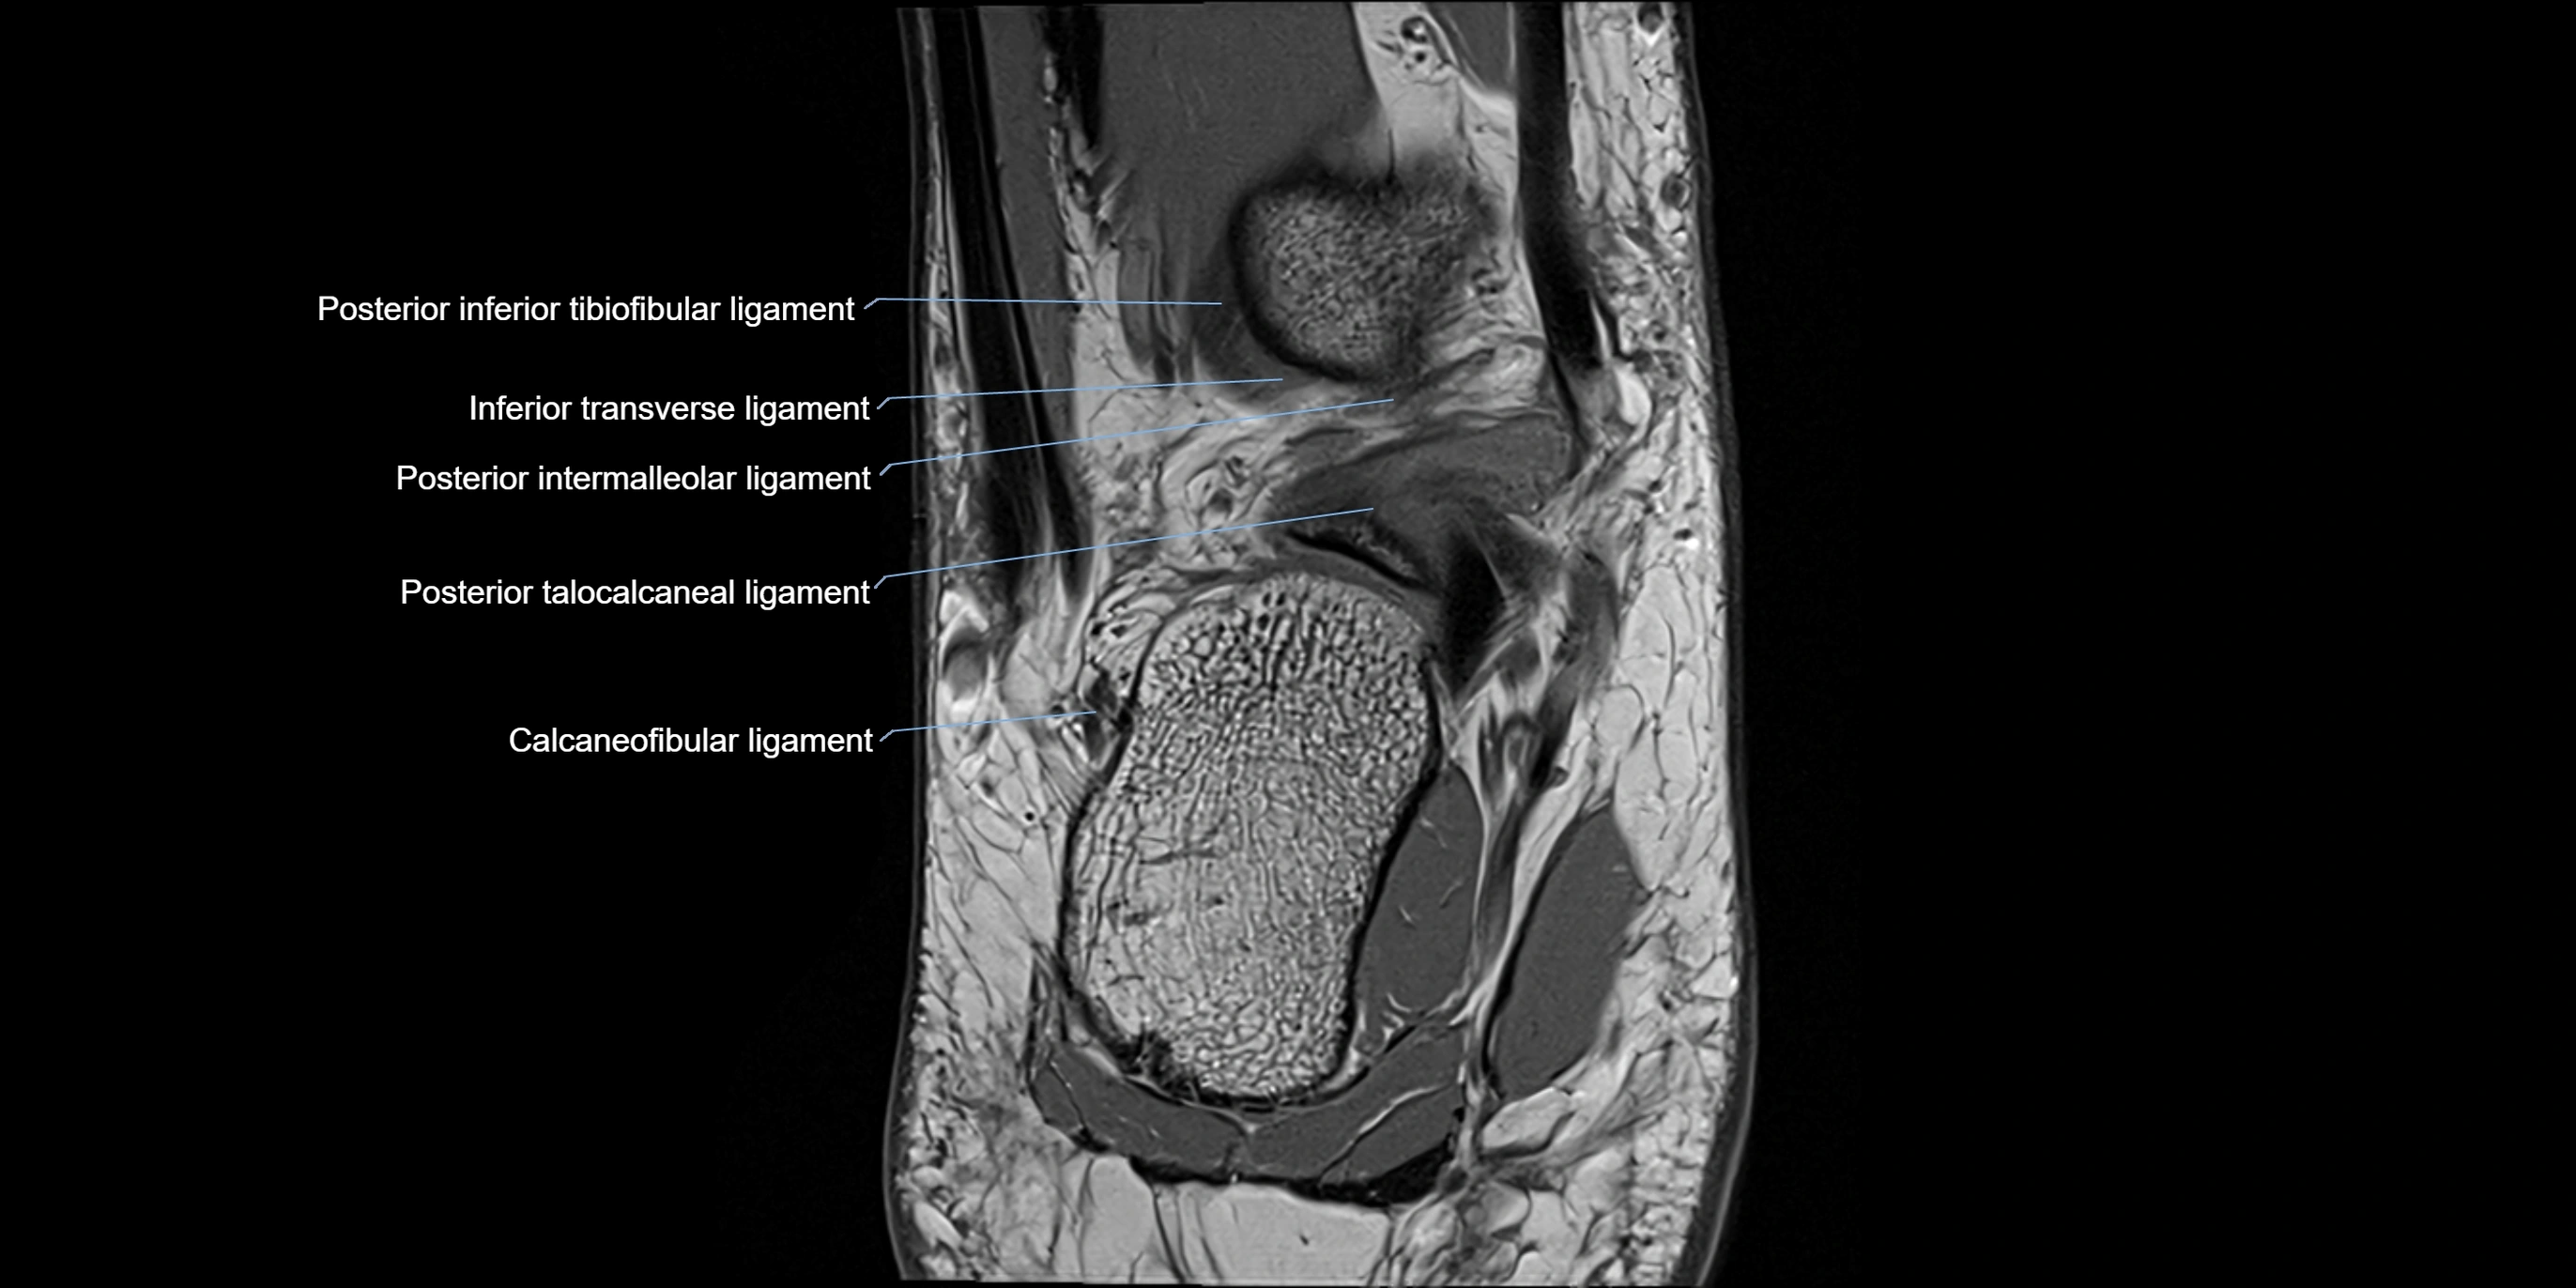

MRI image

image